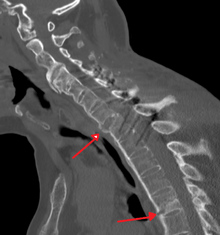

CT scan showing Bamboo spine in ankylosing spondylitis

- The earliest changes in the sacroiliac joints demonstrable by plain x–ray shows erosions and sclerosis.

- Progression of the erosions leads to pseudo-widening of the joint space and bony ankylosis.

- X-ray spine can reveal squaring of vertebrae with spine ossification with fibrous band run longitudinally called syndesmophyte while producing bamboo spine appearance.

- A drawback of X-ray diagnosis is the signs and symptoms of AS have usually been established as long as 8–10 years prior to X-ray-evident changes occurring on a plain film X-ray, which means a delay of as long as 10 years before adequate therapies can be introduced. Options for earlier diagnosis are tomography and MRI of the sacroiliac joints, but the reliability of these tests is still unclear.